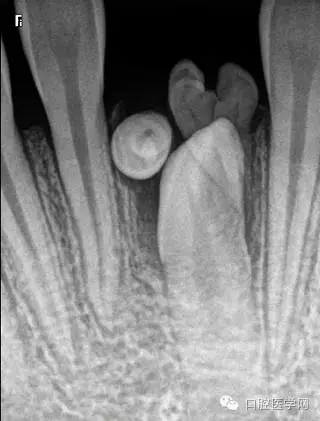

牙中牙

X線表現(xiàn):舌側(cè)窩陷入過深,形似一小牙包于牙髓中。